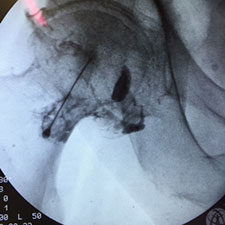

La infiltració de l'articulació sacroilíaca està indicada en el tractament del dolor sacroilíac primari o secundari per sobrecàrrega de l'articulació.

El punt negre visualitza el target on practicar la infiltració. La interlínia assenyalada es refereix a la part posterior de l'articulació.

S'observa l'agulla a l'entrada de l'articulació sacroilíaca. En blanc, s'assenyala el marge lateral de la part anterior de l'articulació. Les fletxes negres posen de manifest el marge medial de la part posterior de l'articulació després d'injectar el contrast.